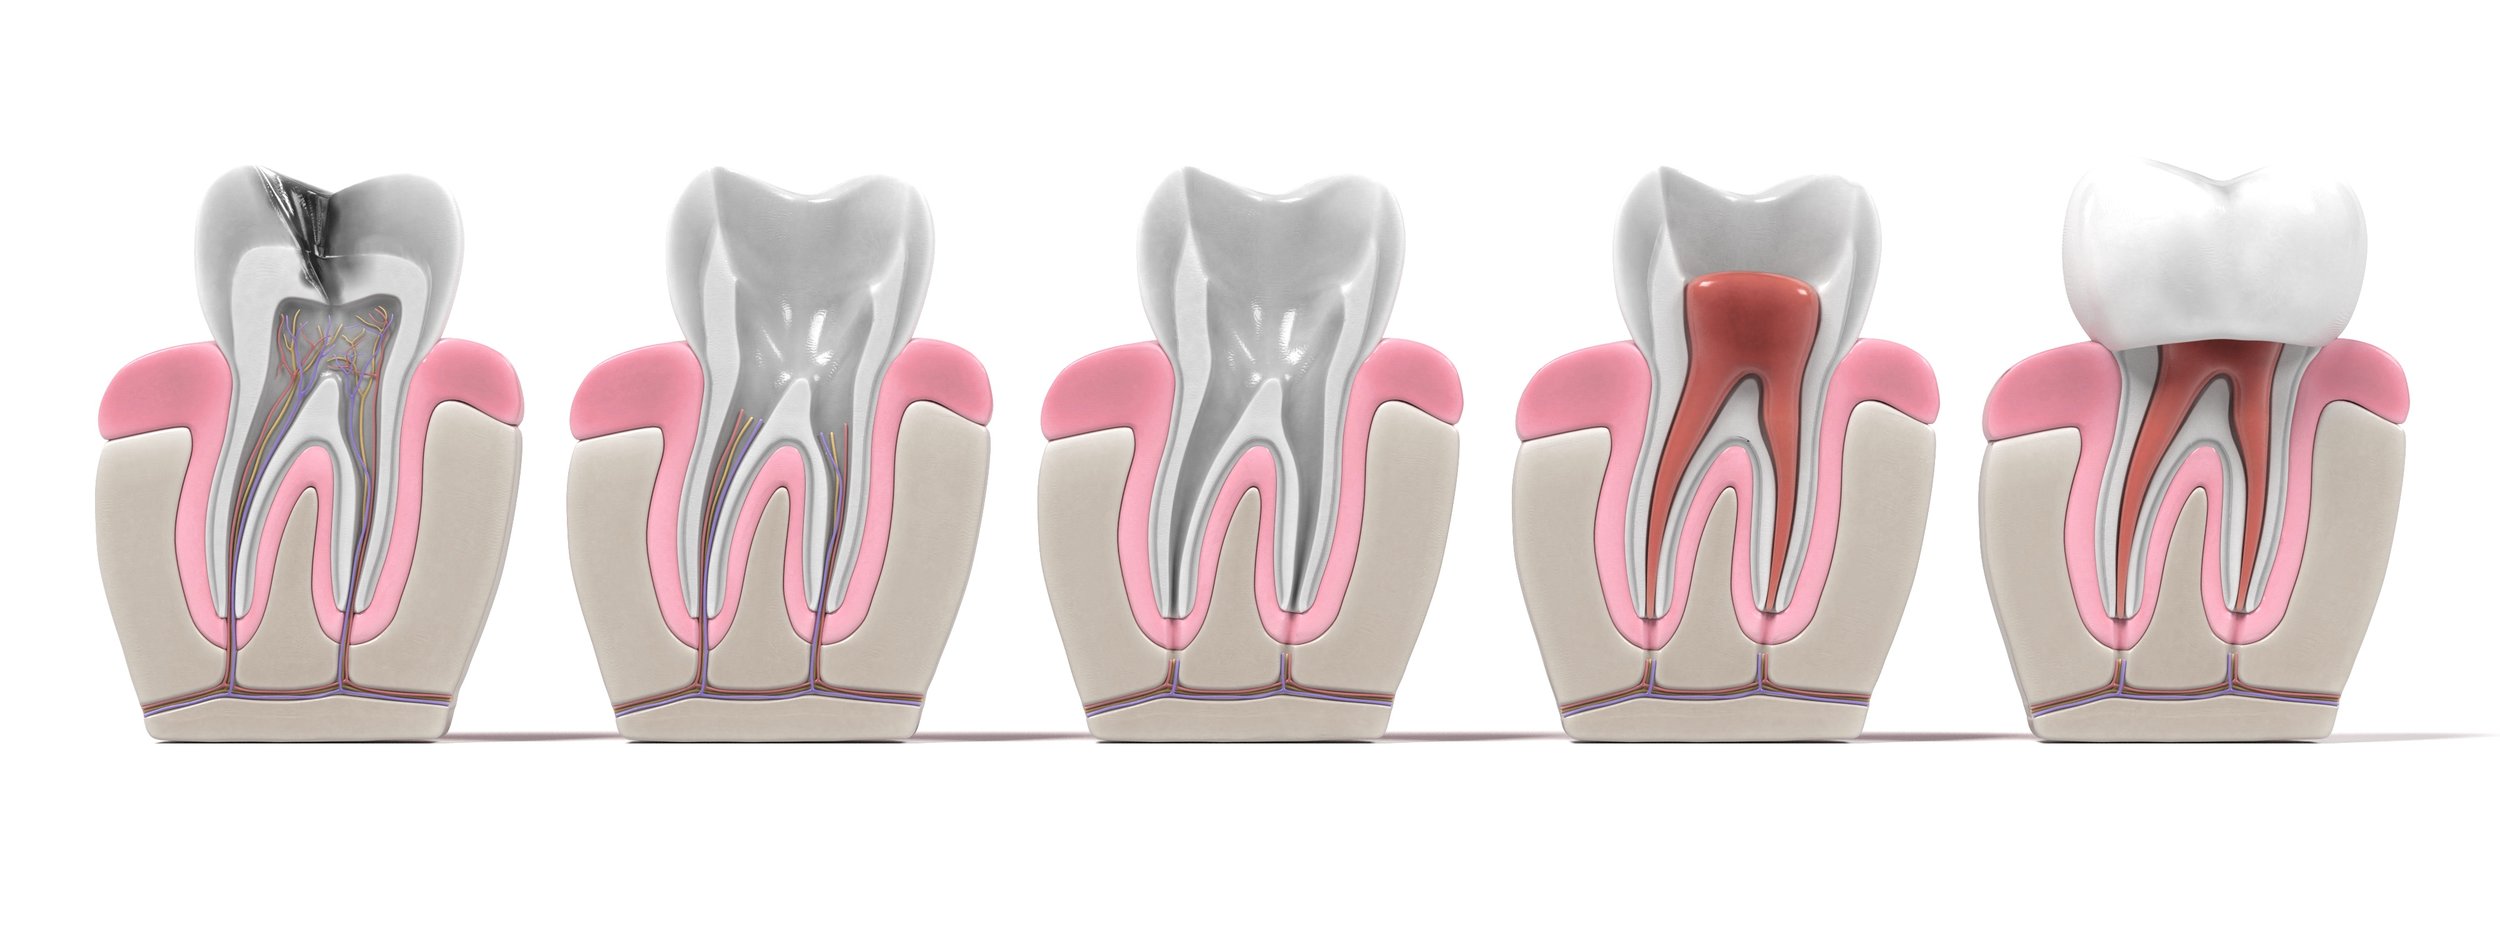

Amíg fogaink épek és egészségesek, addig a fogbél, a pulpa a fog közepén található az őt ellátó erekkel együtt. Az ideget közvetlenül az úgynevezett dentin védi, amely képes bizonyos ingerekre reagálni. Így például sokszor egy szuvas fog, ahol már a dentin is érintett, érzékeny lehet akár egy falat csokira vagy egy pohár hideg vízre is. A dentinnek és az alatta található pulpának kívülről a zománc nyújt biztos védelmet.

Gyökérkezelésre akkor kerül sor, amikor a fog szuvasodása áthatol a zománcrétegen, és a dentinen keresztül eléri a fogbelet. Ilyenkor a szuvasodást okozó baktériumok irritálják a pulpát, amely gyulladással válaszol. Ez a folyamat nagyon heves fájdalommal járhat.

Ebben az esetben az egyetlen megoldás a fogbél elölése, tehát a fog addig élő részének kinyitása és eltávolítása. Az elhalt fog azonban nem jelenti azt, hogy ne tudna továbbra is funkcionálni! Ilyen probléma esetén a fájdalom megszüntetése után gyökértömést készítünk az adott fogba. Ez annyit jelent, hogy minden, eddig élő szövetet el kell távolítani, minden csatornát fel kell tárni, és megfelelő fertőtlenítés után tömőanyaggal kell ellátni azokat, hogy ne engedjünk teret a baktériumok szaporodásának a csatornákban.

A mikroszkópos gyökérkezelés lépései

III. Az idegkamrák feltárásához a fog koronarészének átfúrása következik.

IV. Az idegkamra feltárása után az érintett fogat a szakorvos átvizsgálja, így pontosan megállapítható a gyökércsatornák helye.

V. Az idegkamrák feltárása, és a csatornák helyének meghatározása után következik a gyökércsatornák tisztítása. Az endodontus szakorvos eltávolítja a csatornákból a gyulladást okozó anyagokat, valamint a gyökércsatorna külső rétegét, ugyanis a kezelés célja, hogy csak és kizárólag egészséges szövetek maradjanak.

VI. Az alaposan kitisztított csatornába fertőtlenítő anyagokat juttat a kezelőorvos, hogy a gyulladás maradéktalanul megszűnjön.

VII. Az ideiglenes tömés elhelyezése következik a fogkorona részen. Az ideiglenes tömésre azért van szükség, hogy megóvjuk a kezelt területet, illetve hogy a páciens többé-kevésbé a megszokott módon tudjon étkezni.

VIII. Az ideiglenes tömés után általában egy hét szünet következik. Ez az időszak elegendő szokott lenni arra, hogy bárminemű panasz jelentkezzen. Ha ezalatt az idő alatt elmúlnak a panaszok, a végleges gyökértömés következik, majd a kezelés végéhez érünk. Ha pedig további fájdalom vagy érzékenység lép fel, újabb fertőtlenítés következik, ami egy újabb hét “próbaidőt” jelent. Ez a ciklus addig ismétlődik, míg a gyulladás teljes egészében meg nem szűnik.